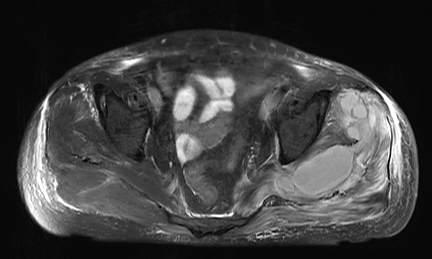

2023年1月3日,患者仍有下肢疼痛不适、尿量减少和水肿症状,实验室检查显示炎症指标进一步升高。双侧髋关节MRI平扫显示左侧髋关节周围软组织异常,提示可能存在感染。如图1:

▲图1:双侧髋关节MRI平扫